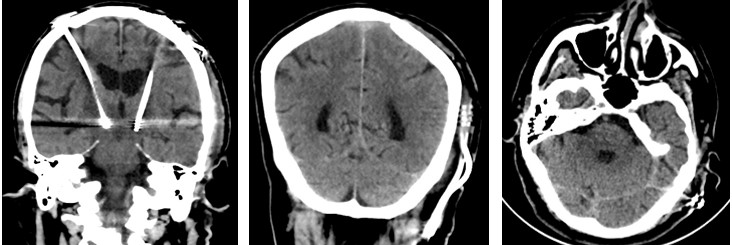

1. CT scan of the brain was done which showed the DBS leads in favourable anatomical place. Image fusion was performed by using present CT scan and old MRI.(FIGURE 2)

FIGURE 2